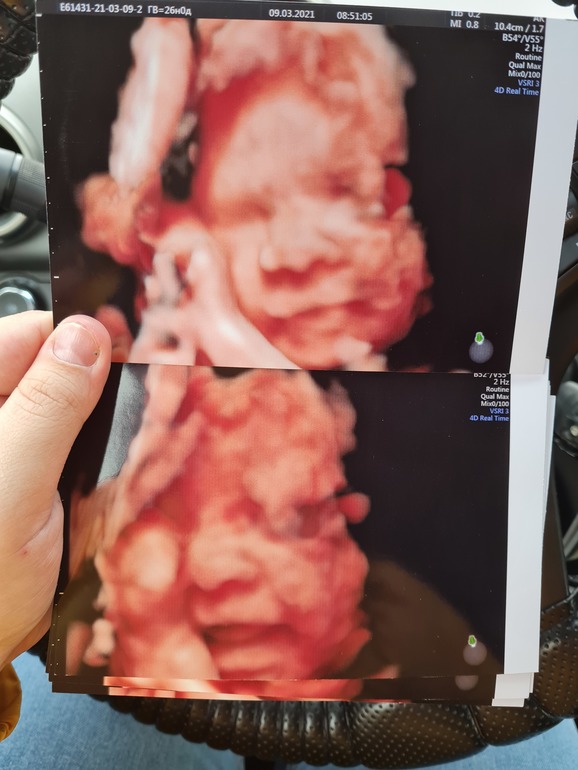

3Д УЗИ в 26 недель, фотопуз)

Вот такая красота получилась😋

Что-то жевала, бормотала, улыбалась и показывала свой маленький язычок)